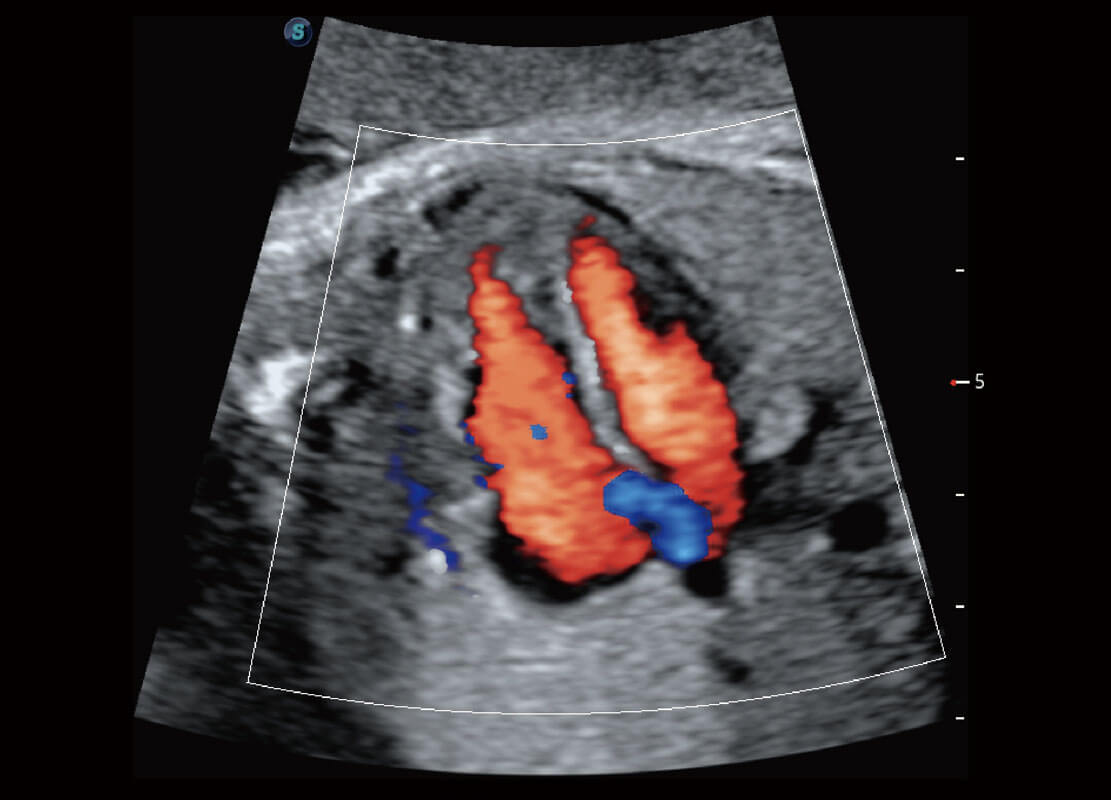

新生儿肝血管癌

P60搭载宽频带线阵探头、宽景成像、弹性成像技术,为您提供乳腺应用方案。P60支持高频相控阵探头、线阵探头、腹部高频探头、腹部微凸探头等,丰富的探头群搭载敏感的彩色血流成像,适用于新生儿多种脏器检测要求,满足新生儿筛查需求。